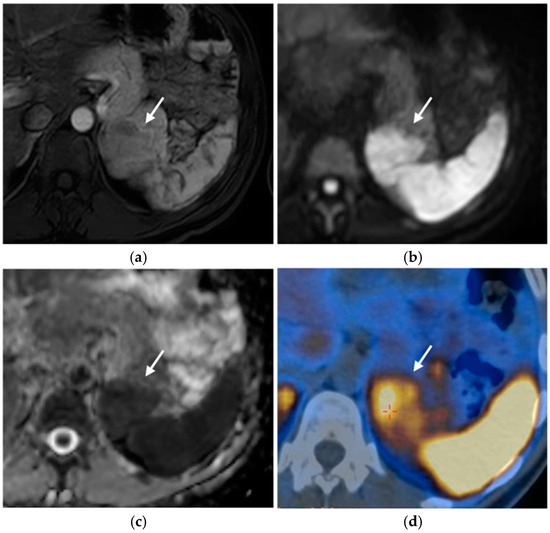

MRI

Nuclear Medicine